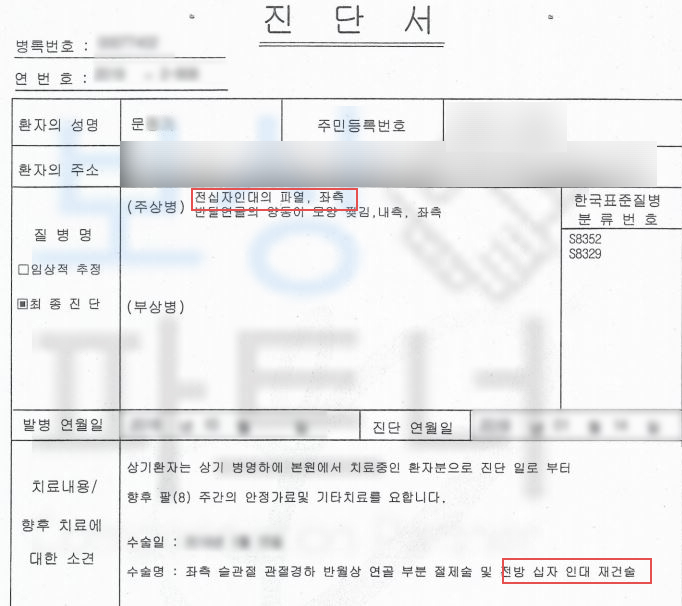

전방십자인대 파열 좌측 s8352

십자인대 재건술을 받으셔야 했죠. 십자인대 재건술을 받았음에도 거동 시에무릎이 흔들거리거나 다리가 툭툭 떨어지는 느낌이 있다면 후유증 보상 즉 후유장해보상 알아보세요.